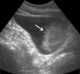

Infiltrating carcinoma of bladder

Bladder cancer is any of several types of cancer arising from the tissues of the urinary bladder. Symptoms include blood in the urine, pain with urination, and low back pain.Risk factors for bladder cancer include smoking, family history, prior radiation therapy, frequent bladder infections, and exposure to certain chemicals. [Source: Wikipedia ]